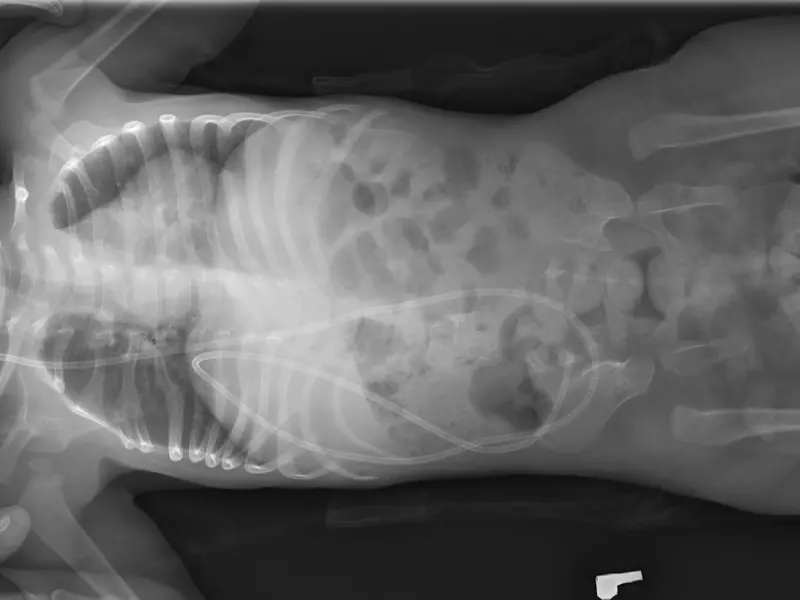

Stopa końsko-szpotawa jest drugą po zwichnięciu stawu biodrowego najczęściej spotykaną wadą wrodzoną u dzieci (zdj. 1 i 2). Może być też wadą nabytą, wtórną do zaburzeń nerwowo-mięśniowych, takich jak przepuklina oponowo-rdzeniowa czy przebyte zapalenie polio, lub wtórną do działających sił zewnętrznych,

We wrodzonej stopie końsko-szpotawej zniekształcenie dotyczy głównie kości stępu, które w chwili urodzenia dziecka są w większości chrzęstne. Znajdują się one w maksymalnie wymuszonych pozycjach zgięcia, przywiedzenia (rotacji wewnętrznej) i odwrócenia. Kość skokowa jest ustawiona w zgięciu podeszwowym, jej szyjka jest skręcona podeszwowo, a głowa ma kształt klina. Kość łódkowata jest przemieszczona przyśrodkowo w pobliże kostki przyśrodkowej, tworzy powierzchnię stawową z przyśrodkową częścią głowy kości skokowej. Pięta jest przywiedziona (zrotowana do wewnątrz) i odwrócona pod kością skokową, natomiast ścięgna mięśni piszczelowego przedniego, prostownika długiego palucha i prostownika długiego palców są przemieszczone przyśrodkowo [1].